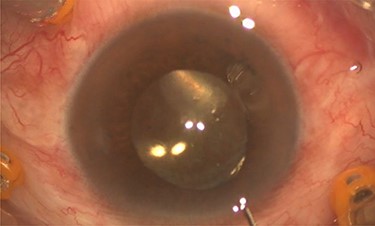

Pars plana vitrectomy and posterior capsulotomy were done. After placing three 23-gauge trocars, a corneal paracentesis was made. After IOL tapping, the entrapped turbid fluid escaped to the anterior chamber (Fig. 3). Anterior vitrectomy and posterior capsulotomy were done using a 23-gauge vitrector (Fig. 4).

Intra-operative photo showed egression of turbid fluid to the anterior chamber.